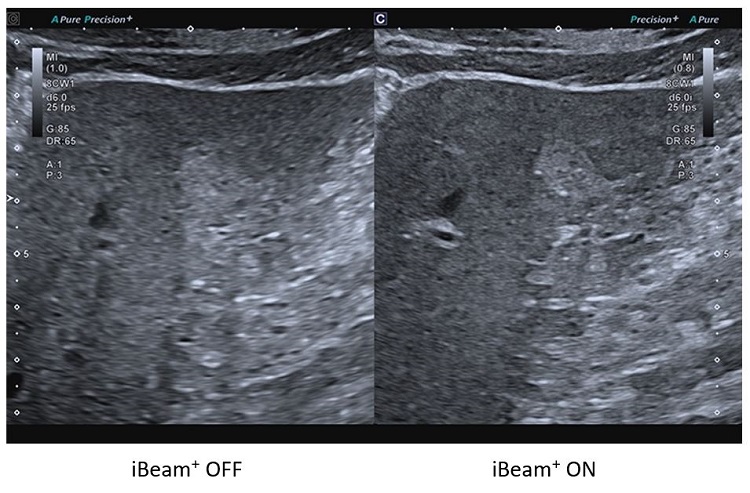

iBeam+

Особливі технології обробки зображень Aplio можуть допомогти покращити якість зображення шляхом зменшення шумів, посилення сигналу та покращення візуалізації.

Система обробки зображень iBeam+ використовує вдосконалену обробку сигналів для більш точного й гнучкого керування ультразвуковими променями, що робить зображення більш глибоким і чітким.

• Вища роздільна здатність

• Краще проникнення

• Краща однорідність

• Вища частота кадрів